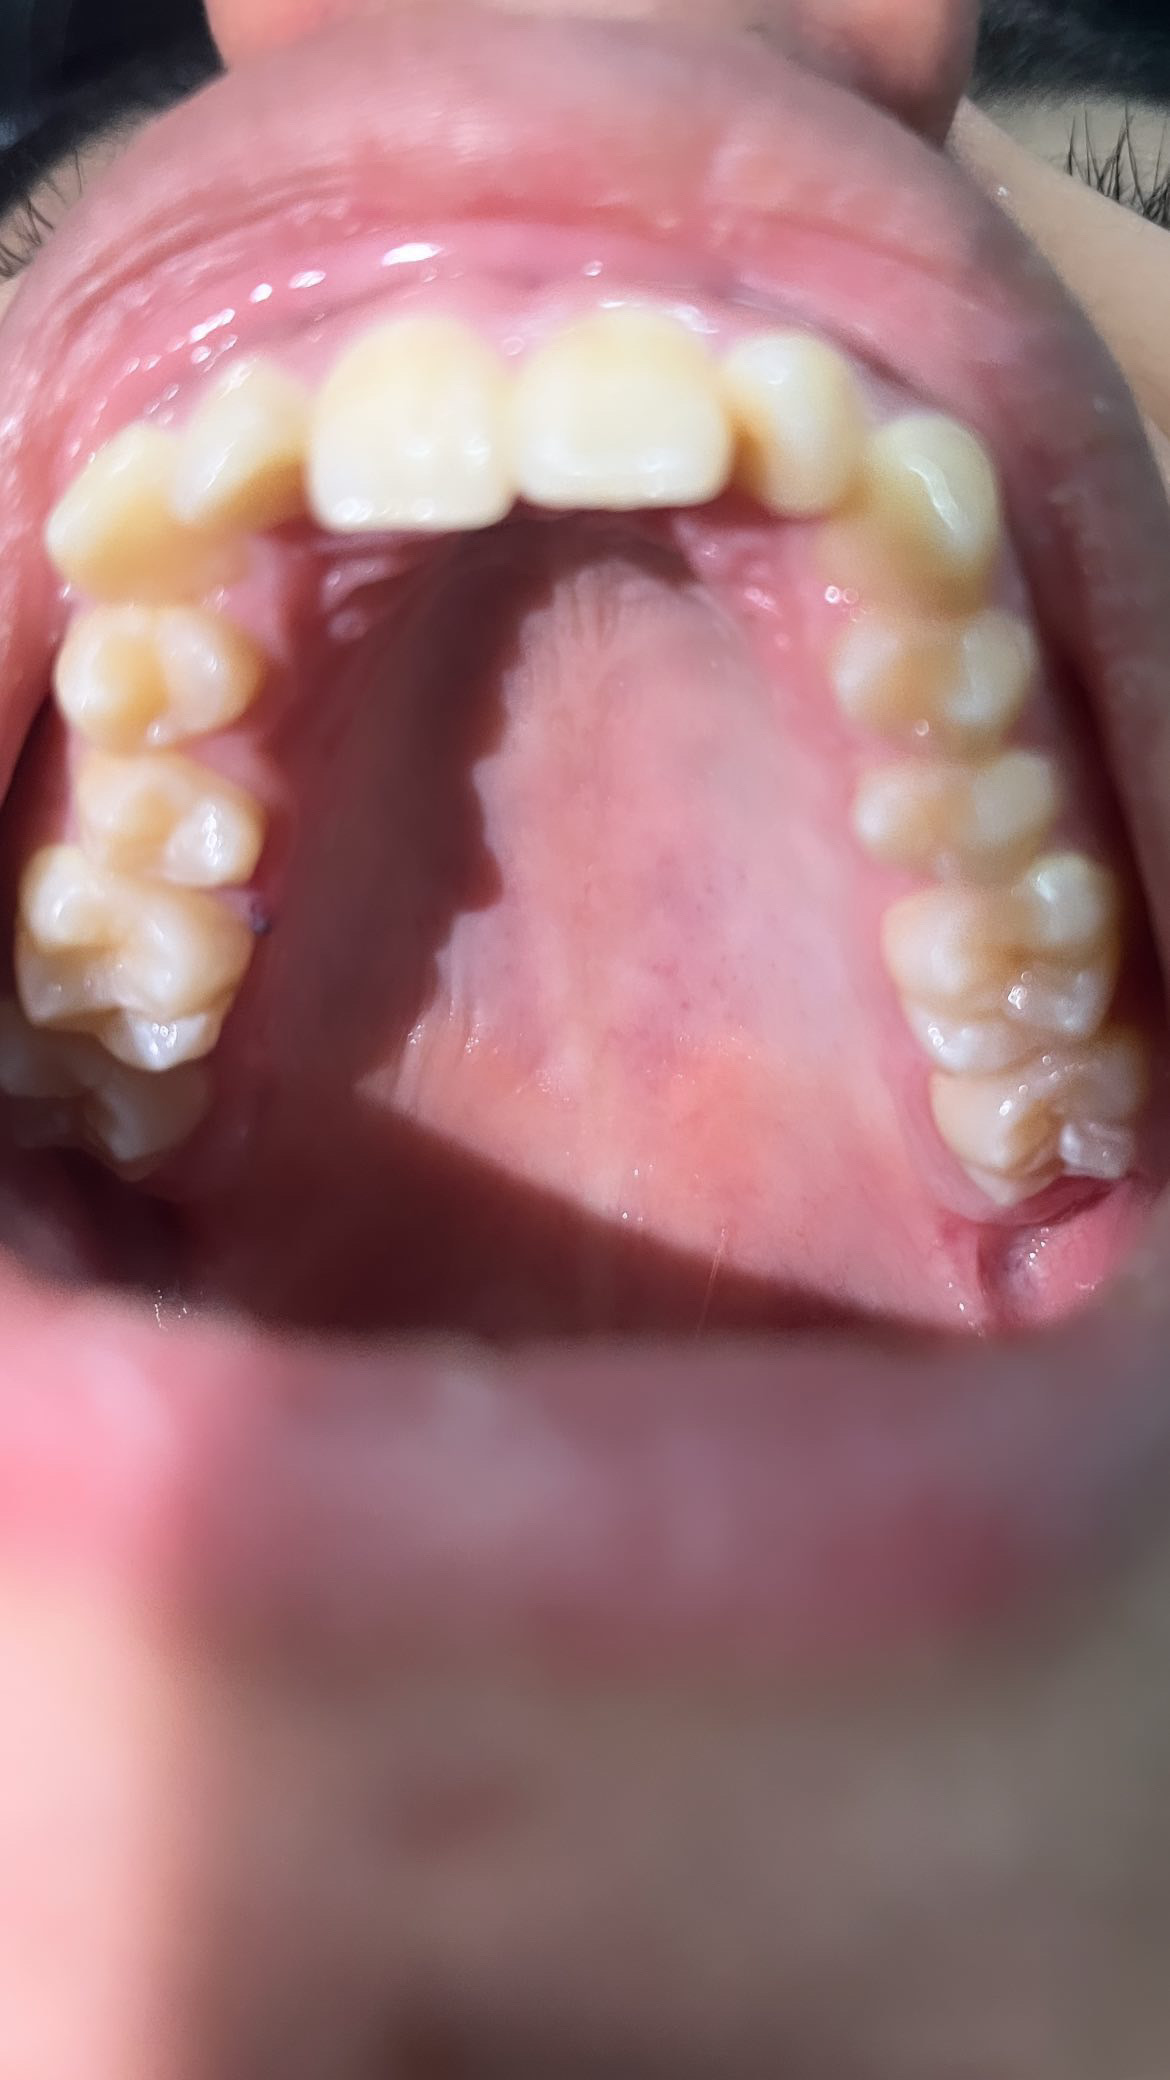

My primary incisors are prominent but they bulge inwards my secondary incisors are really sideways and my canines are decent but maybe can be straighter

But my first incisors need to be pushed outwards and secondary incisors need to face straight instead of side

Your palate is near death teir get palate expander for upper and lower jaw